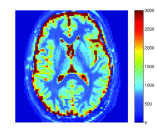

In MRI, data is acquired in the Fourier domain of the spatial image (a.k.a. k-space). The acquisition time of a high resolution, single contrast 3D MRI lasts a substantial amount of time. Since MRF is based on rapid acquisition of hundreds of different contrasts, severe under-sampling is performed in k-space to obtain the temporal resolution required for MRF. Figure 1 demonstrates the effect of fully sampled versus under-sampled data, acquired with spiral trajectories and recovered using the inverse non uniform fast Fourier transform (NUFFT) Fessler and Sutton [2003]. It can be seen that the under-sampled data is blurred and introduces aliasing artifacts. Figure 2 illustrates the noise and under-sampling artifacts of a representative brain voxel intensity as function of time, where the data is acquired with an MRF sequence based on fast imaging with steady state precession (FISP) Jiang et al. [2015]. Clearly, under-sampling also introduces a substantial level of noise in the time domain. In addition, MRF uses a dictionary with discrete values, while QMRI values are continuous. This leads to quantization error, depending on the values represented in the dictionary.

Figure 6 shows the resulting maps for the recovery of T1, T2 and PD obtained with the various algorithms against the reference (left). The corresponding error maps of each method versus the reference are shown in Fig. 7. To allow detailed view of the reconstruction results for the reader, Fig. 6 shows a zoomed region for each map.

It can be seen that both FLOR and MBIR-MRF outperform BLIP reconstruction results, when using 5% of sampled data by utilizing the low rank property. In addition, FLOR provides a lower error compared to MBIR-MRF. The details in the FLOR maps are comparable to those obtained by the original MRF algorithm using 100% of the noise-free data. Due to the very low sampling ratio in our experiments (measured as the number of samples divided by the number of pixels in the image), conventional MRF using 5% of the data did not provide valuable reconstruction results and is therefore omitted in this analysis.